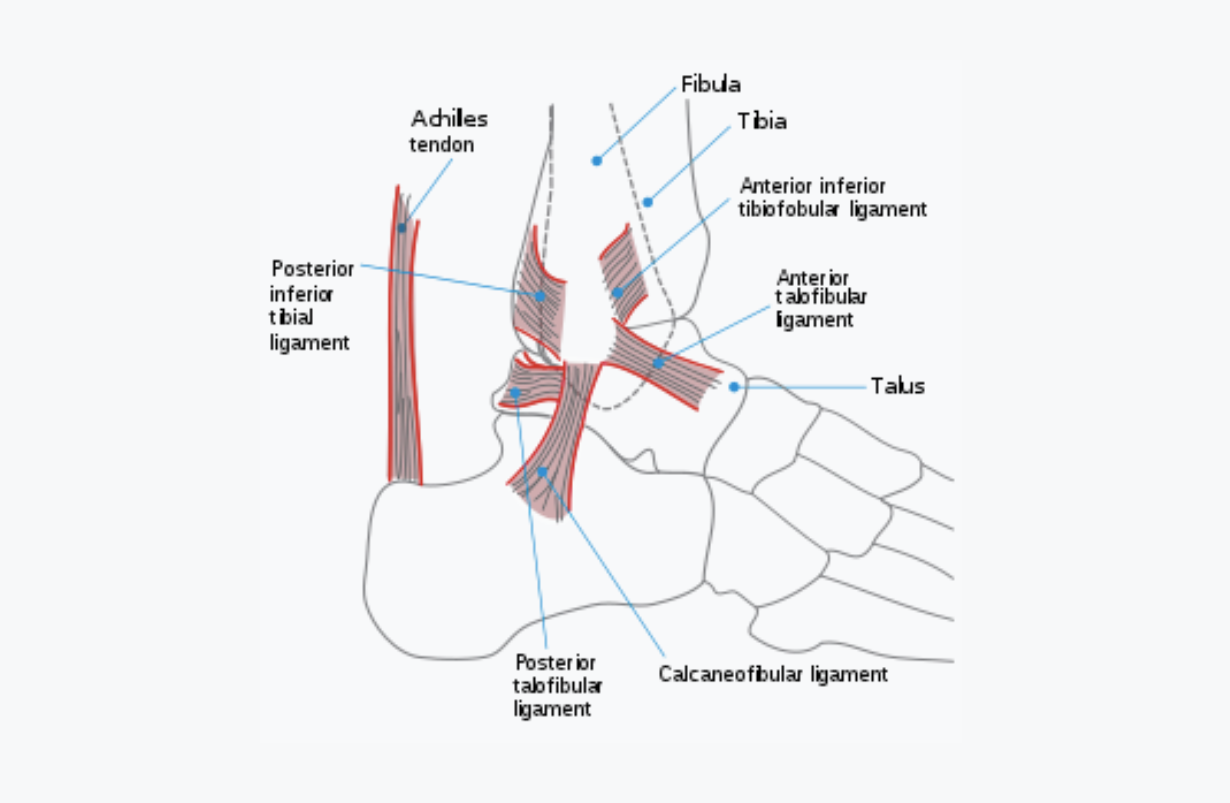

Sprained Ankle

Tearing of the fibres that hold the bones of the foot to the bones of the lower leg. Over 90% are at the lateral side of the foot. BENEFICIAL POSES: Garudasana (seated), Dhanurasana, Supta Padangusthasana I, Supta Padangusthasana II, Supta Padangusthasana III. (See video for III.) EXPLANATION: Pressure on the ankle must be avoided to allow healing to progress. Yoga can increase range of motion at the hip, thereby lessening ankle strain, and the twists and turns required of the ankle during standing support on the ankle-knee-hip support chain. Supta Padangusthasana I, II and III should be done holding above the ankle. Later, after healing has been allowed to take its course - 6 to 8 weeks - standing poses may be introduced slowly and cautiously, at first using a wall for support, in order to re-strengthen the muscles. guiding ankle activity. See picture of lateral side of ankle, where at least 9 of 10 ankle sprains occur. REFERENCES: The authors found no studies using yoga for ankle sprain. The above recommendations are based on general Rehabilitation Medicine principles and Dr. Fishman's clinical experience.